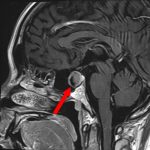

下垂体腺腫

No.’25_102 手術前1

No.’25_102 手術前2